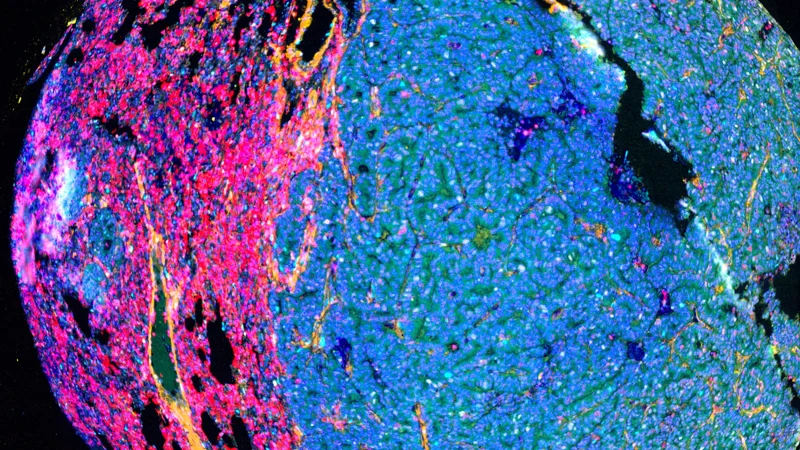

Tissue AI: The future of tumor imaging - The Jackson Laboratory

Tissue AI reveals not just where cancer cells are, but how they communicate, evolve, and shape their surroundings.